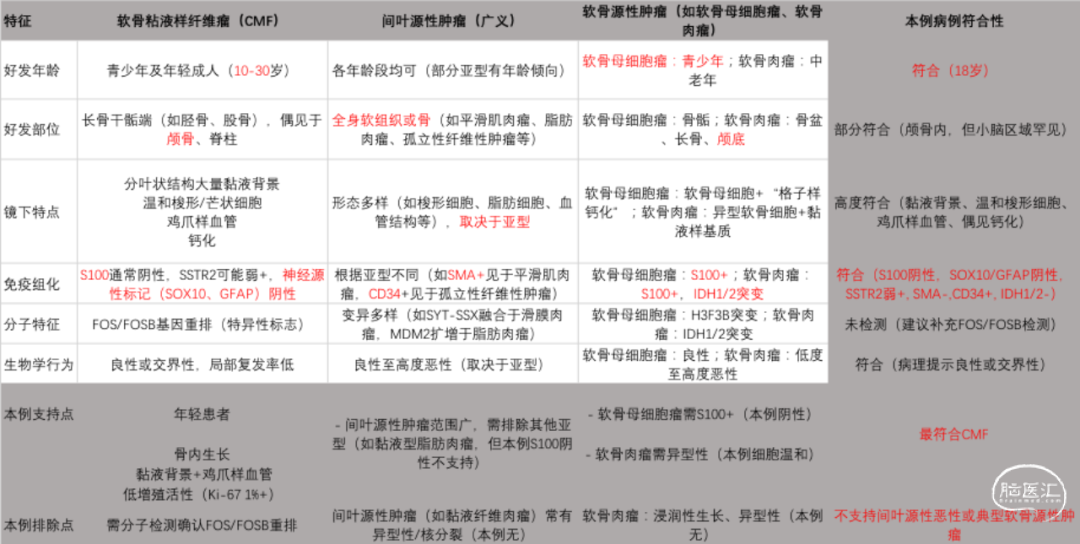

患者入院完善术前检查,头颅CT提示:右侧小脑半球-枕叶混杂密度肿块,大小约71*37mm,内见钙化,邻近颅骨骨质破坏、变薄,第四脑室受压(图1、图2)。进一步完善头颅增强MRI提示右侧颞枕部占位,脑外起源考虑,软骨肉瘤可能,血管瘤型脑膜瘤或血管瘤待排(图3)。

图1. 头颅CT影像,见右侧小脑半球-枕叶混杂密度肿块,大小约71*37mm,内见钙化。

图2. 头颅CT骨窗像,见肿块邻近颅骨骨质破坏、变薄。